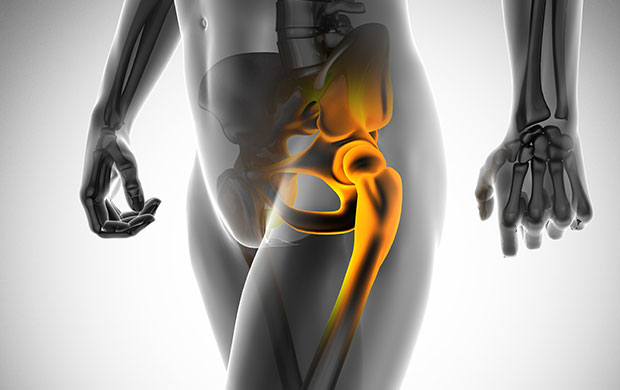

고관절은 엉덩이관절이라고도 불리우며, 보통 알고있는 골반위치에 있고, 공처럼 둥글게 생긴 대퇴골두가 글러브가 감싼듯한 모양으로 비구에 맞물려 있어요.

이렇듯 고관절은 오목하게 들어간 비구와 둥근 공모양의 대퇴골두로 이루어져 있으며 골반과 다리를 이어주는 우리 몸의 핵심 관절인데요. 그리고 고관절은 골반을 통해 전달되는 체중을 지탱해주고 걷기와 달리기같은 다리 운동들을 가능하게 해주는 관절이기도 해요.

고관절은 체중의 3배에서 달리기를 할때에는 최대 10배까지의 무게를 감당하는데, 고관절의 질병으로 인해 기능을 잃게 되면 보행의 어려움과 함께 일상생활에 불편함을 초래하게 돼요. 고관절은 대부분 퇴행성 질환으로 노화가 되어가면서 관절의 손상으로 인해 발생하고, 고관절 자체 구조적인 문제, 주변 근육과 인대의 문제, 척주와 골반 문제 등 여러가지 원인이 있으며, 특히나 퇴행성 고관절염, 대퇴 골두 무혈상 괴사, 대퇴골 경부 골절, 퇴행성 관절염, 급성 활액막염 등 여러가지 원인이 있어요.